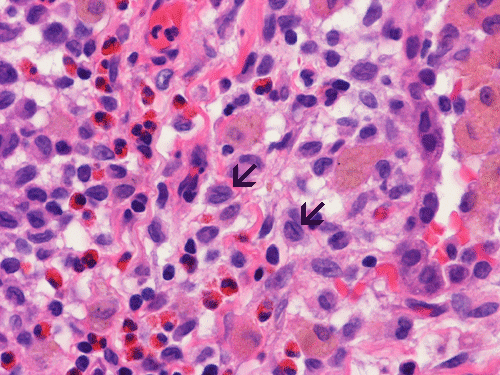

At scanning magnification (Panel A), the lung parenchyma is replaced by some coalescing fibrous nodules. The degree of involvement is variable at different fragments (Panel B and C). In the less affected areas, there are some fibrotic thickening of the septa (Panel C). In some areas, the changes are minimal and the pleural appear to be uninvolved (Panel D and E). In low to medium magnifications, these nodules of fibrosis contains a large number of hemosiderin laden macrophages (Panel F and G) admixed with fibrous tissue. The diagnostic tissue, however, is present in areas with increased cellularity. In these areas, there is a background of cells with a moderate amount of cytoplasm and bland nuclei. Some of these nuclei have kidney shape (arrow in Panel H). In some areas, many of the nuclei have a deep nuclear groove that resemble a coffee bean (arrow in Panel I). In the third type of areas, the nuclear grooving is not distinct (Panel J). Prominent eosinophilic infiltrations are almost always present. Immunohistochemistry on CD1a revealed many positive cells (Panel L). Also present in the specimen are multiple small blood vessels with thickened intima (Panel K). A Movat pentachrome stain demonstrates an internal elastic layer in these vessels and confirms that these are arteries (Panel M and N).

Pathologically, PLCH can be broadly divided into an early or cellular stage and a late or fibrotic stage. Demonstration of LCs is of critical importance for a correct diagnosis. The morphology of LCs is similar to LCH in other organs. LCs are characterized by a deep nuclear groove which lead to “coffee bean-shaped” or “kidney-shaped” nuclei. In most cases, the level of atypia and pleomorphism is low. A moderate amount of amphophilic to weakly eosinophilic cytoplasm is present. The cytoplasmic membrane is indistinct. Eosinophils and chronic inflammatory cells, varying from scant to abundant, are present. Except for a scant frankly pleomorphic cases, the level of pleomorphism and atypia is minimal to low. Eosinophilic abscesses with central necrosis may be present. Immunohistochemically, LCs are similar to their normal counter parts and are positive for CD1a and S100. At the ultrastructural level, Birbeck granules can be demonstrated. For most cases, the diagnosis can be established by histopathologic criteria but these additional features help to confirm the diagnosis.

In the early stage of PLCH, there are interstitial infiltrates composed of LCs, lymphocytes, macrophages, eosinophils, plasma cells and fibroblasts 4. The infiltrates enlarge to form nodules centered on the small airways. Brown pigmented macrophages (smokers macrophages) are present in and around the nodules. Eosinophils tend to localize at the innermost layer of the nodules, where LCs can be most easily found in the thickened interstitium. Associated patchy interstitial and airspace organization or respiratory bronchiolitis may be present. Other smoking related changes are also common. Cavitation often occurs within the nodules which represents either an airway remenant or de novo cavitation as the inflammatory infiltrate enlarges. There is centripetal replacement of the nodules by fibroblasts which produce the classic stellate lesions of PLCH. As the disease progresses, the number of nodules, cavitary granulomas and fibrotic scars increase in number.